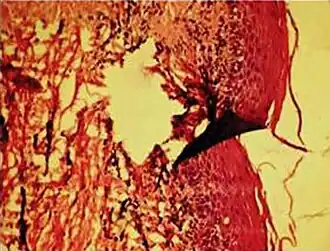

Formalin pigment artifacts -